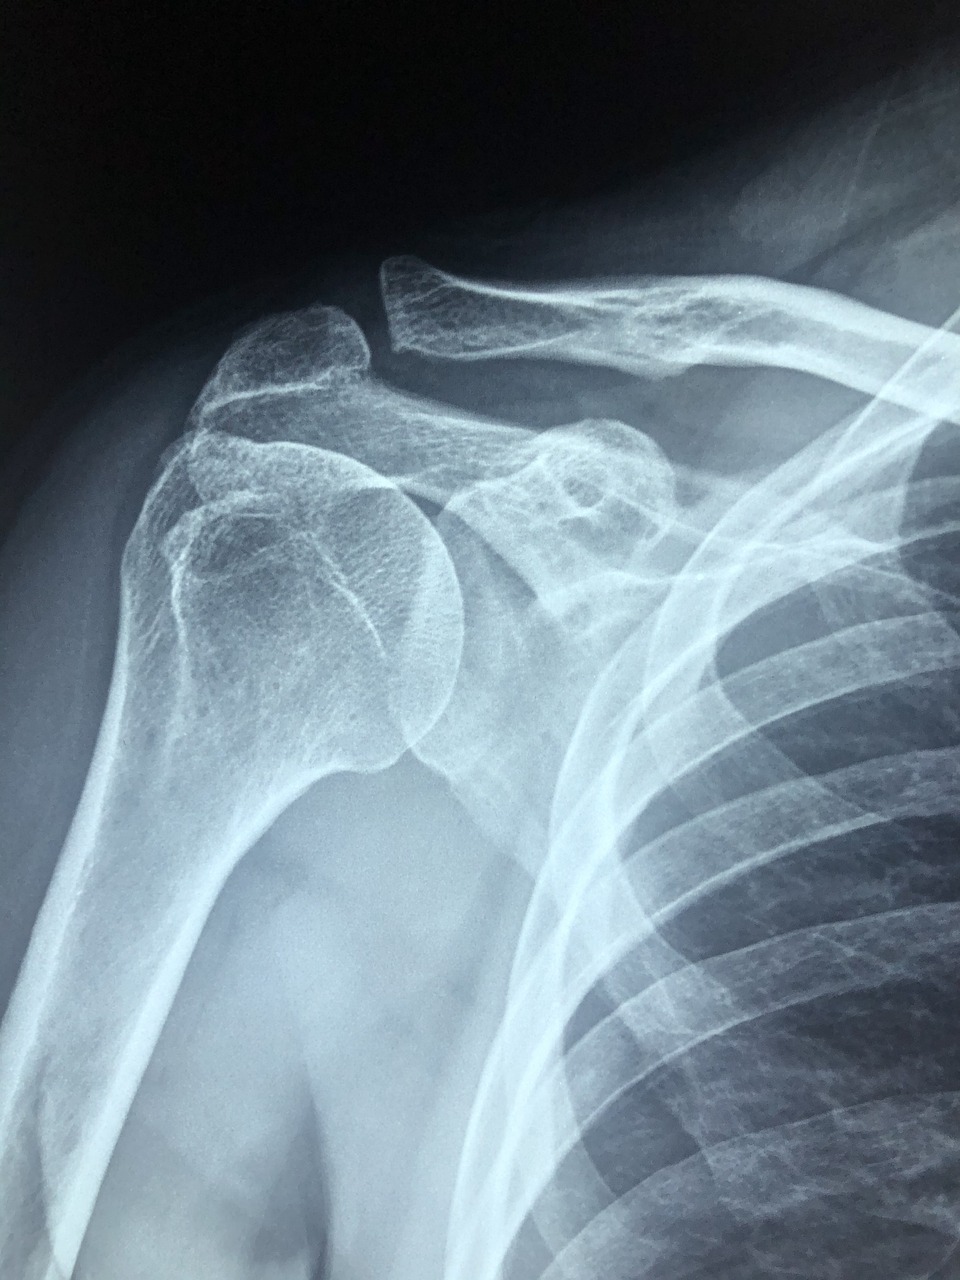

수술 후 첫 6주는 조직이 붙는 회복기의 핵심 단계입니다. 이 시기엔 회전근개파열 수술 부위를 자극하지 않으면서, 어깨가 굳지 않도록 수동운동을 해주는 게 중요합니다.